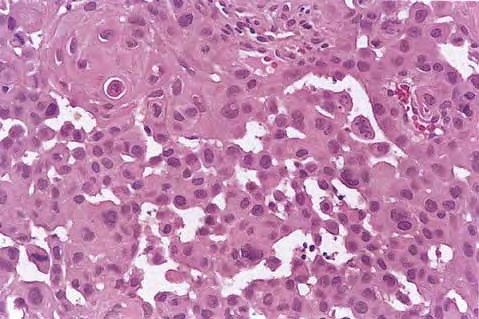

Squamous Cell Carcinoma = الكارسينوما شائكة الخلايا